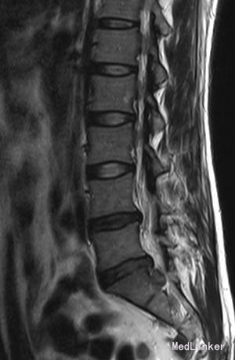

诊断:腰椎间盘突出症 (腰5/骶1髓核游离型) VAS评分:9分 ODI评分:96% 疼痛剧烈,右下肢难以伸直,坐卧不宁;给予常规脱水,激素,止痛等治疗无效;不同意手术,反复要求保守治疗。 保守治疗3天,患者疼痛仍无明显缓解,同意行手术治疗 手术方案:椎板间隙入路PELD 术后予以止痛,脱水,小剂量激素等治疗, 术后第二天:右下肢麻木疼痛明显缓解。查体:右小腿后侧及足背外侧皮肤触觉恢复;右足拇跖屈肌力4+级;右侧直腿抬高试验(-);右侧跟腱反射仍减弱。 术后第5天:出现右小腿及足底针刺样疼痛症状加重,麻木感,伴有右下肢间歇性抽搐,次数较频繁,以夜间为甚。查体:腰椎活动无明显受限,右小腿后面及右足背外侧触痛明显;双下肢屈伸肌力、肌张力基本正常;右侧直腿抬高试验(-),右侧跟腱反射仍减弱。 予以加大NSAID及地米治疗,效果不明显,夜间疼痛难以入睡。复查腰椎MRI,未见髓核再脱出,减压彻底 诊断:考虑右侧骶1神经根神经病理性疼痛 治疗: 普瑞巴林 75mg Bid;神经妥乐平 2# Bid; 阿米替林 25mg Bid 外加神经营养治疗 治疗1周后,症状明显缓解

术后10周:右侧臀部及右下肢烧灼样疼痛及皮肤触痛缓解,右下肢间歇性抽搐消失,偶感腰背部酸痛。查体:右足背外侧仍稍许麻木,无痛觉过敏,双下肢肌力正常,双直腿抬高试验(-).